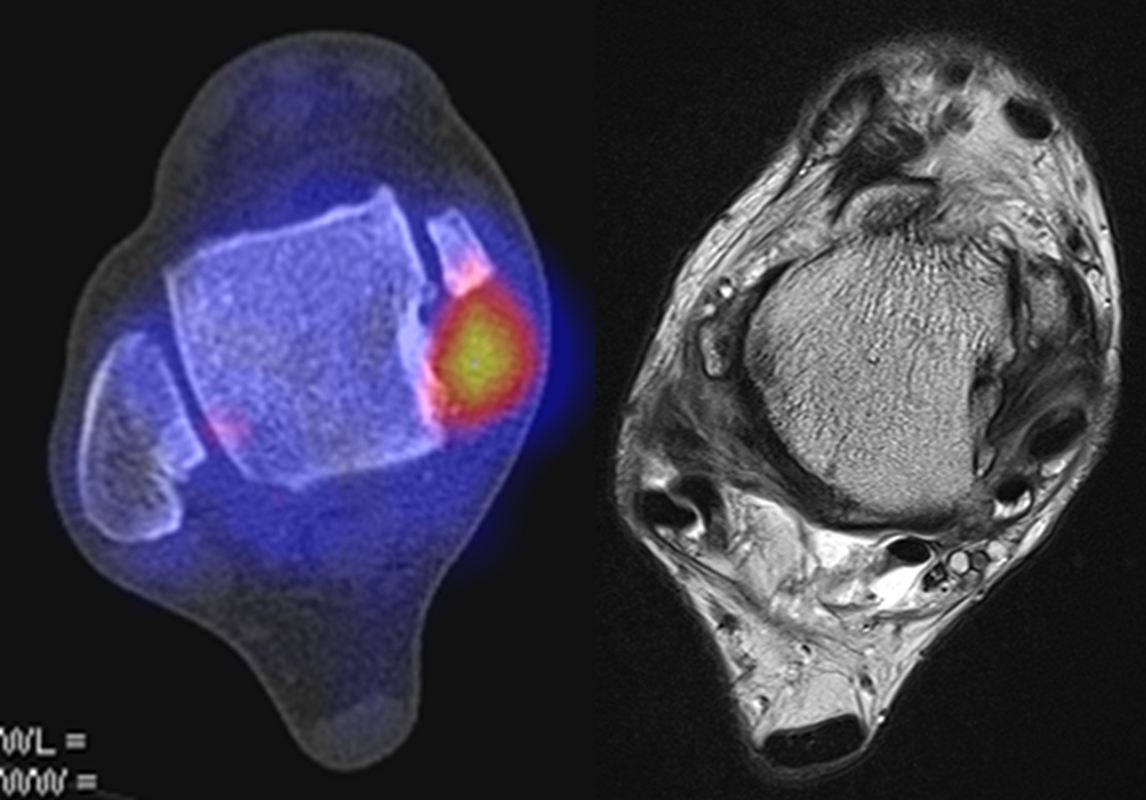

Abbildung 2.1.

Bildbeispiele symptomatische OCL

Zum Lesen der Bildbeschreibung und zur Vollansicht bitte das Bild anklicken. Bild: H. C. Rischke

Abbildung 2.2.

Bilder eines Patienten mit Z. n. mehrfachen Sprunggelenksdistorsionen in der Vergangenheit, besonders heftige Distorsion des linken Sprunggelenkes 5 Wochen vor der Untersuchung. Die SPECT/CT zeigt eine instabile osteochondrale Läsion mit deutlicher Aktivierung.

Abbildung 2.3.

Klärung bei Schmerzen im rechten OSG bei OCL an der medialen Talusschulter. Z. n. OSG-Distorsion vor 2 Jahren und Z. n. OSG-Fraktur / Syndesomosenruptur. Ausgedehnte OCL, hier jedoch kein erhöhter Knochenmetabolismus; lediglich Nachweis einer Stressreaktion im Bereich der Synchondrose eines Os trigonum als Schmerzursache.